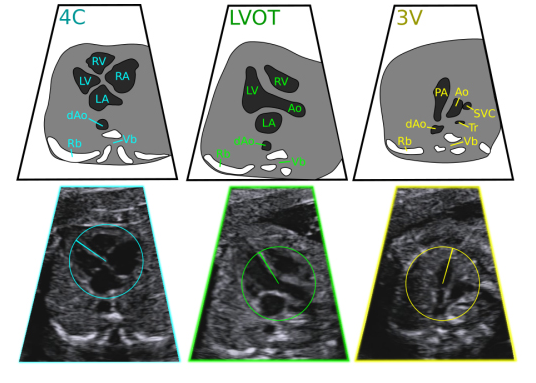

கருஎக்கோகார்டியோகிராம்என்பதுபிறப்புக்குமுந்தையஅல்ட்ராசவுண்ட்பரிசோதனையாகும், இதுபிறவிஇதயக்குறைபாடுஇருப்பதைக்கண்டறியகருவின்இதயத்தின்அமைப்புமற்றும்செயல்பாட்டைஆய்வுசெய்கிறது.

கருமருத்துவநிபுணர்களால்செய்யப்படும்பிறமகப்பேறுக்குமுற்பட்டஸ்கேனிங்பரிசோதனைகளைப்போலவேஇதுஅல்ட்ராசவுண்ட்தொழில்நுட்பத்தைப்பயன்படுத்துகிறது.